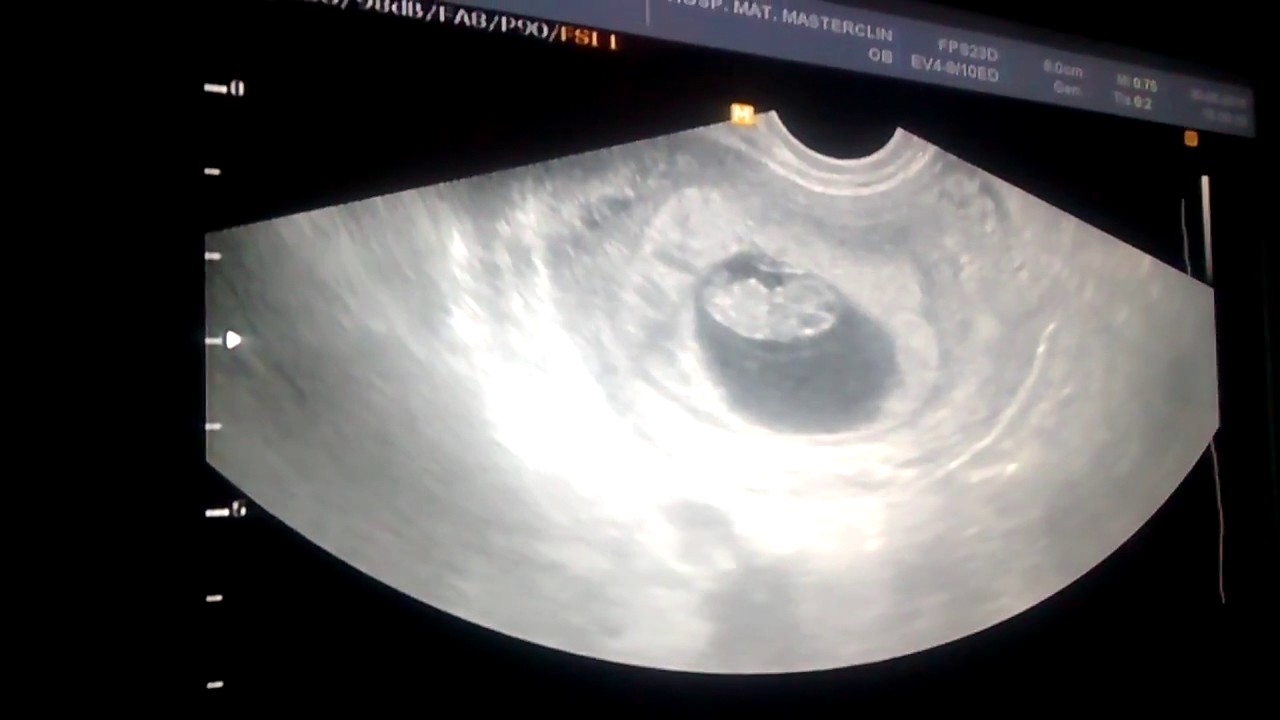

Grau 1: com pouco sangramento e com poucas contrações uterinas. O feto não é afetado. Este é o mais frequente. Grau 2: há mais contrações uterinas e ocorre sangramento moderado. O aumento da frequência cardíaca do feto também pode ser um indicador. Grau 3: ocorre no caso em que a placenta se separa completamente da parede uterina, embora seja muito raro.. Os exames de imagem desempenham um papel importante no diagnóstico de descolamento de placenta no início da gravidez: Ultrassonografia: A ultrassonografia é útil para identificar o hematoma retroplacentário, que é caracterizado por uma área de sangramento com aspecto heterogêneo e hiperecogênico em comparação com a placenta.

O descolamento de placenta é mais frequente no segundo trimestre de gravidez, embora possa ocorrer desde o início da gestação. O diagnóstico é feito por exame clínico e ultrassonografia. Os principais fatores de risco para um descolamento prematuro de placenta são: Traumas (acidentes automobilísticos, trauma abdominal direto);. O descolamento prematuro da placenta (DPP), também conhecido como placenta abrupta ou desprendimento placentário, é uma complicação incomum, porém grave da gravidez, na qual a placenta descola-se parcial ou completamente do útero antes da hora do parto. A DPP é um problema potencialmente fatal, pois a perda de contato entre a placenta e.